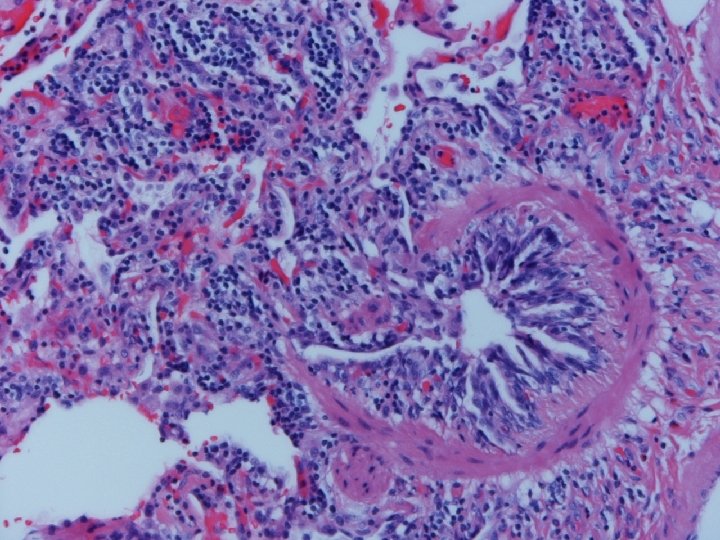

Lung biopsy revealed chronic bronchiolitis/ hypersensitivity pneumonitis (extrinsic allergic alveolitis) with opinion from Mayo Clinic path arriving on 3/30/04. “Hot tub lung due to MAC”. I recommended Prednisone 20 mg. daily, but she had major psychiatric complications for which Seroquel was added and prednisone reduced. X-ray, spirometry, and symptoms resolved. Prednisone tapered and stopped in late May. Recurrence of symptoms and rash in August/September.

Acute HP • Clinical-Abrupt • Lab-ESR, IGG, RA, CRP, LDH, BAL lymphocytosis, restrictive physiology • CXR-micronodular interstitial, but freq. normal-HRCT needed, but not absolute • Histopathology-poorly formed, noncaseating interstitial granulomas, monos, giant cells

Subacute or Intermittent HP • Clinical-gradual cough, dyspnea, fatigue, anorexia, wt. loss, malaise; tachypnea and rales • Lab-BAL lymphocytosis, hypoxemia. Restrictive or mixed spiro, decreased DLCO • CXR-nml, micronodular, reticular. HRCT micronodules, ground glass, emphysema, fibrosis • Histopathology- noncaseating granulomas, bronchiolitis with or w/o organizing pneumonia

Chronic Progressive HP • Clinical-insidious cough, dyspnea, fatigue, weight loss, clubbing • Lab-not very helpful-BAL lymphocytosis but not crisp; restrictive, but usually mixed. DL always reduced, and exertional hypoxemia • CXR-may be normal, but usually progressive fibrosis; emphysema often • Histopathology-granulomatous pneumonia, BO with or w/o OP, fibrosis